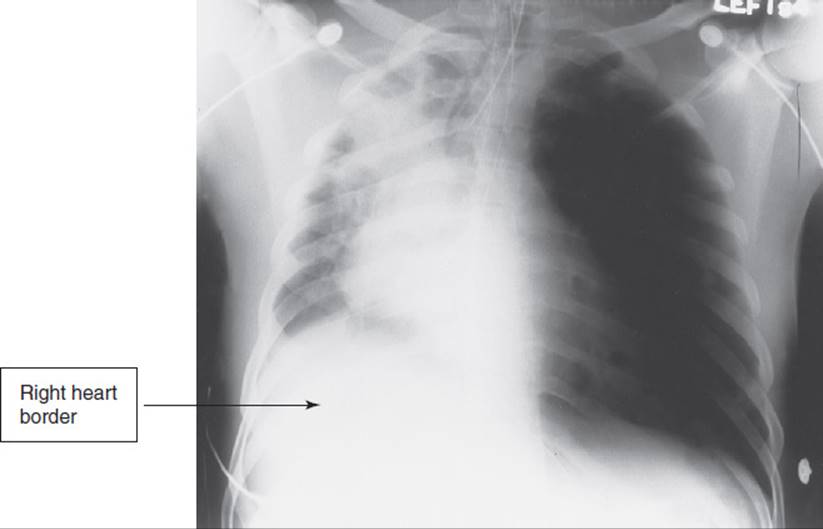

Ventilator-associated pneumonia (VAP), the most frequent type of nosocomial infection in the ICU, occurs in up to 30% of intubated patients.89 VAP consists of a pulmonary inflammatory reaction and sepsis in patients who are mechanically ventilated for a minimum of 48 hours. It is difficult to accurately diagnose, and because the underlying illness of critically ill patients often has a high mortality rate, it is difficult to differentiate to what extent mechanical ventilation contributes to the risk of nosocomial pneumonia.90 Historically, clinical findings have been used to diagnose pneumonia yet have not been shown to have sufficient accuracy, leading to the overuse of antimicrobial therapy (Table 19-7). Quantitative cultures are recommended to determine the bacterial load in a tracheal sample to differentiate colonization from infection and avoid overutilization of antibiotics. Clinicians may also see the use of biomarkers to assist in the diagnosis of VAP in the future.89

TABLE 19-7 Criteria for the Diagnosis of Pneumonia